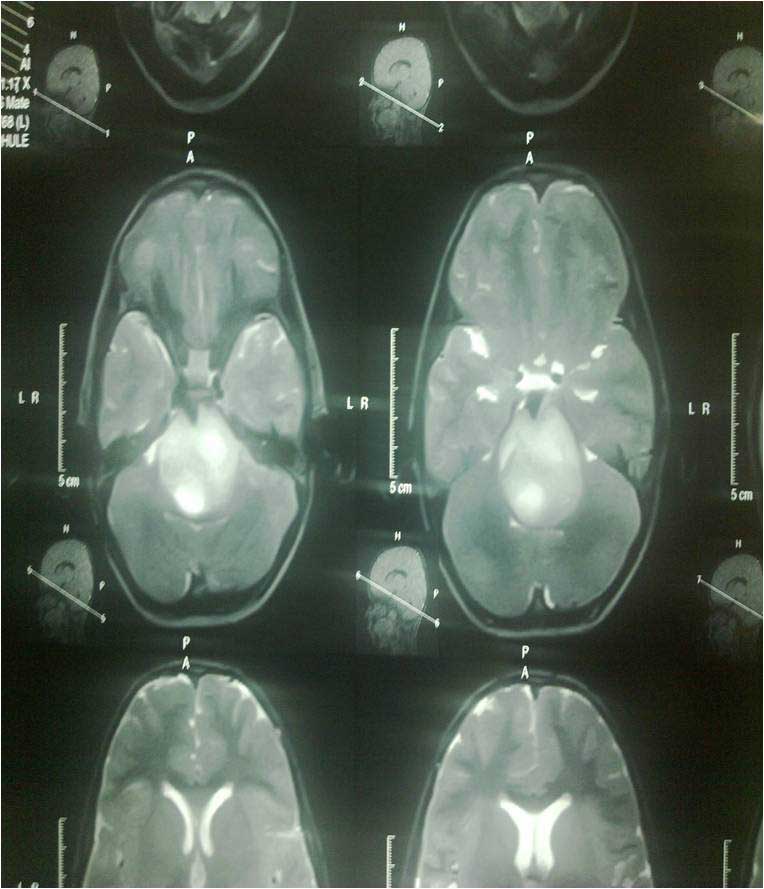

Brainstem Glioma

• Brainstem Glioma